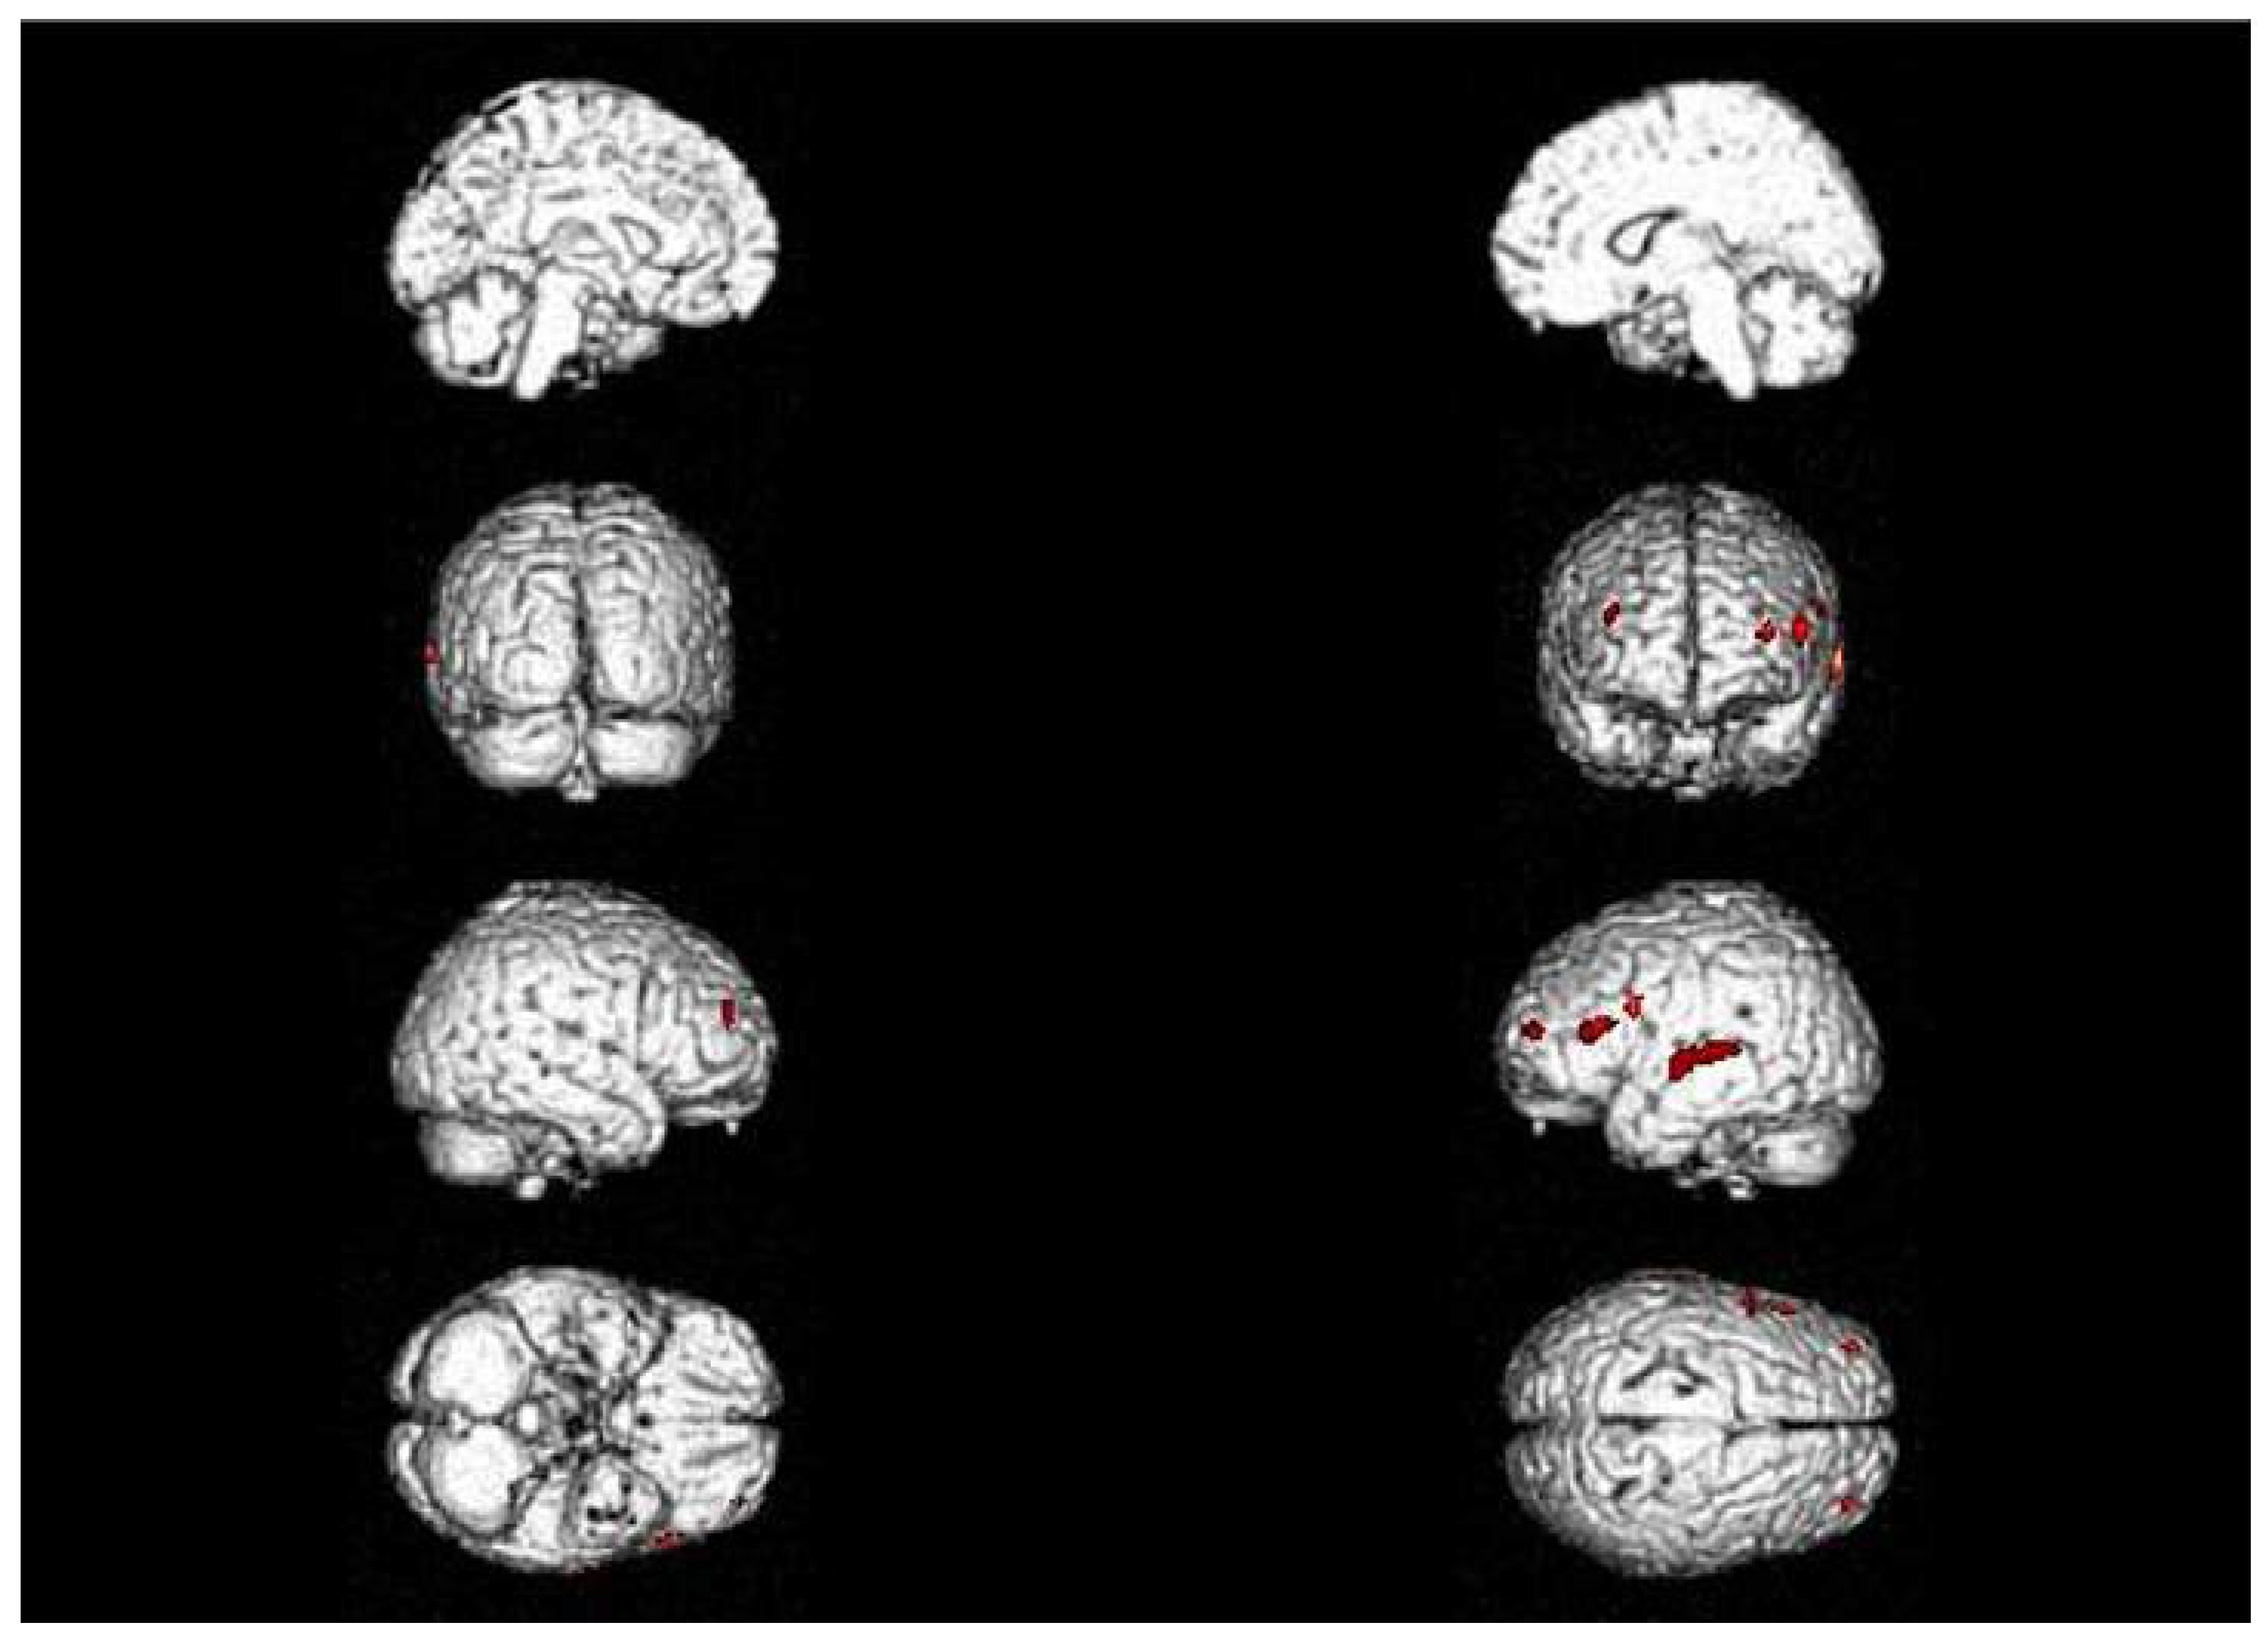

| 2013 | FDG-PET | Hypometabolism in the right and left premotor cortex |

| 2015 | Neurological assessment FDG-PET | Mild isolated motor speech disorder hypometabolism; more extensive involving left temporal gyrus, frontal gyrus bilaterally, cingulate, caudate, and thalamus bilaterally |